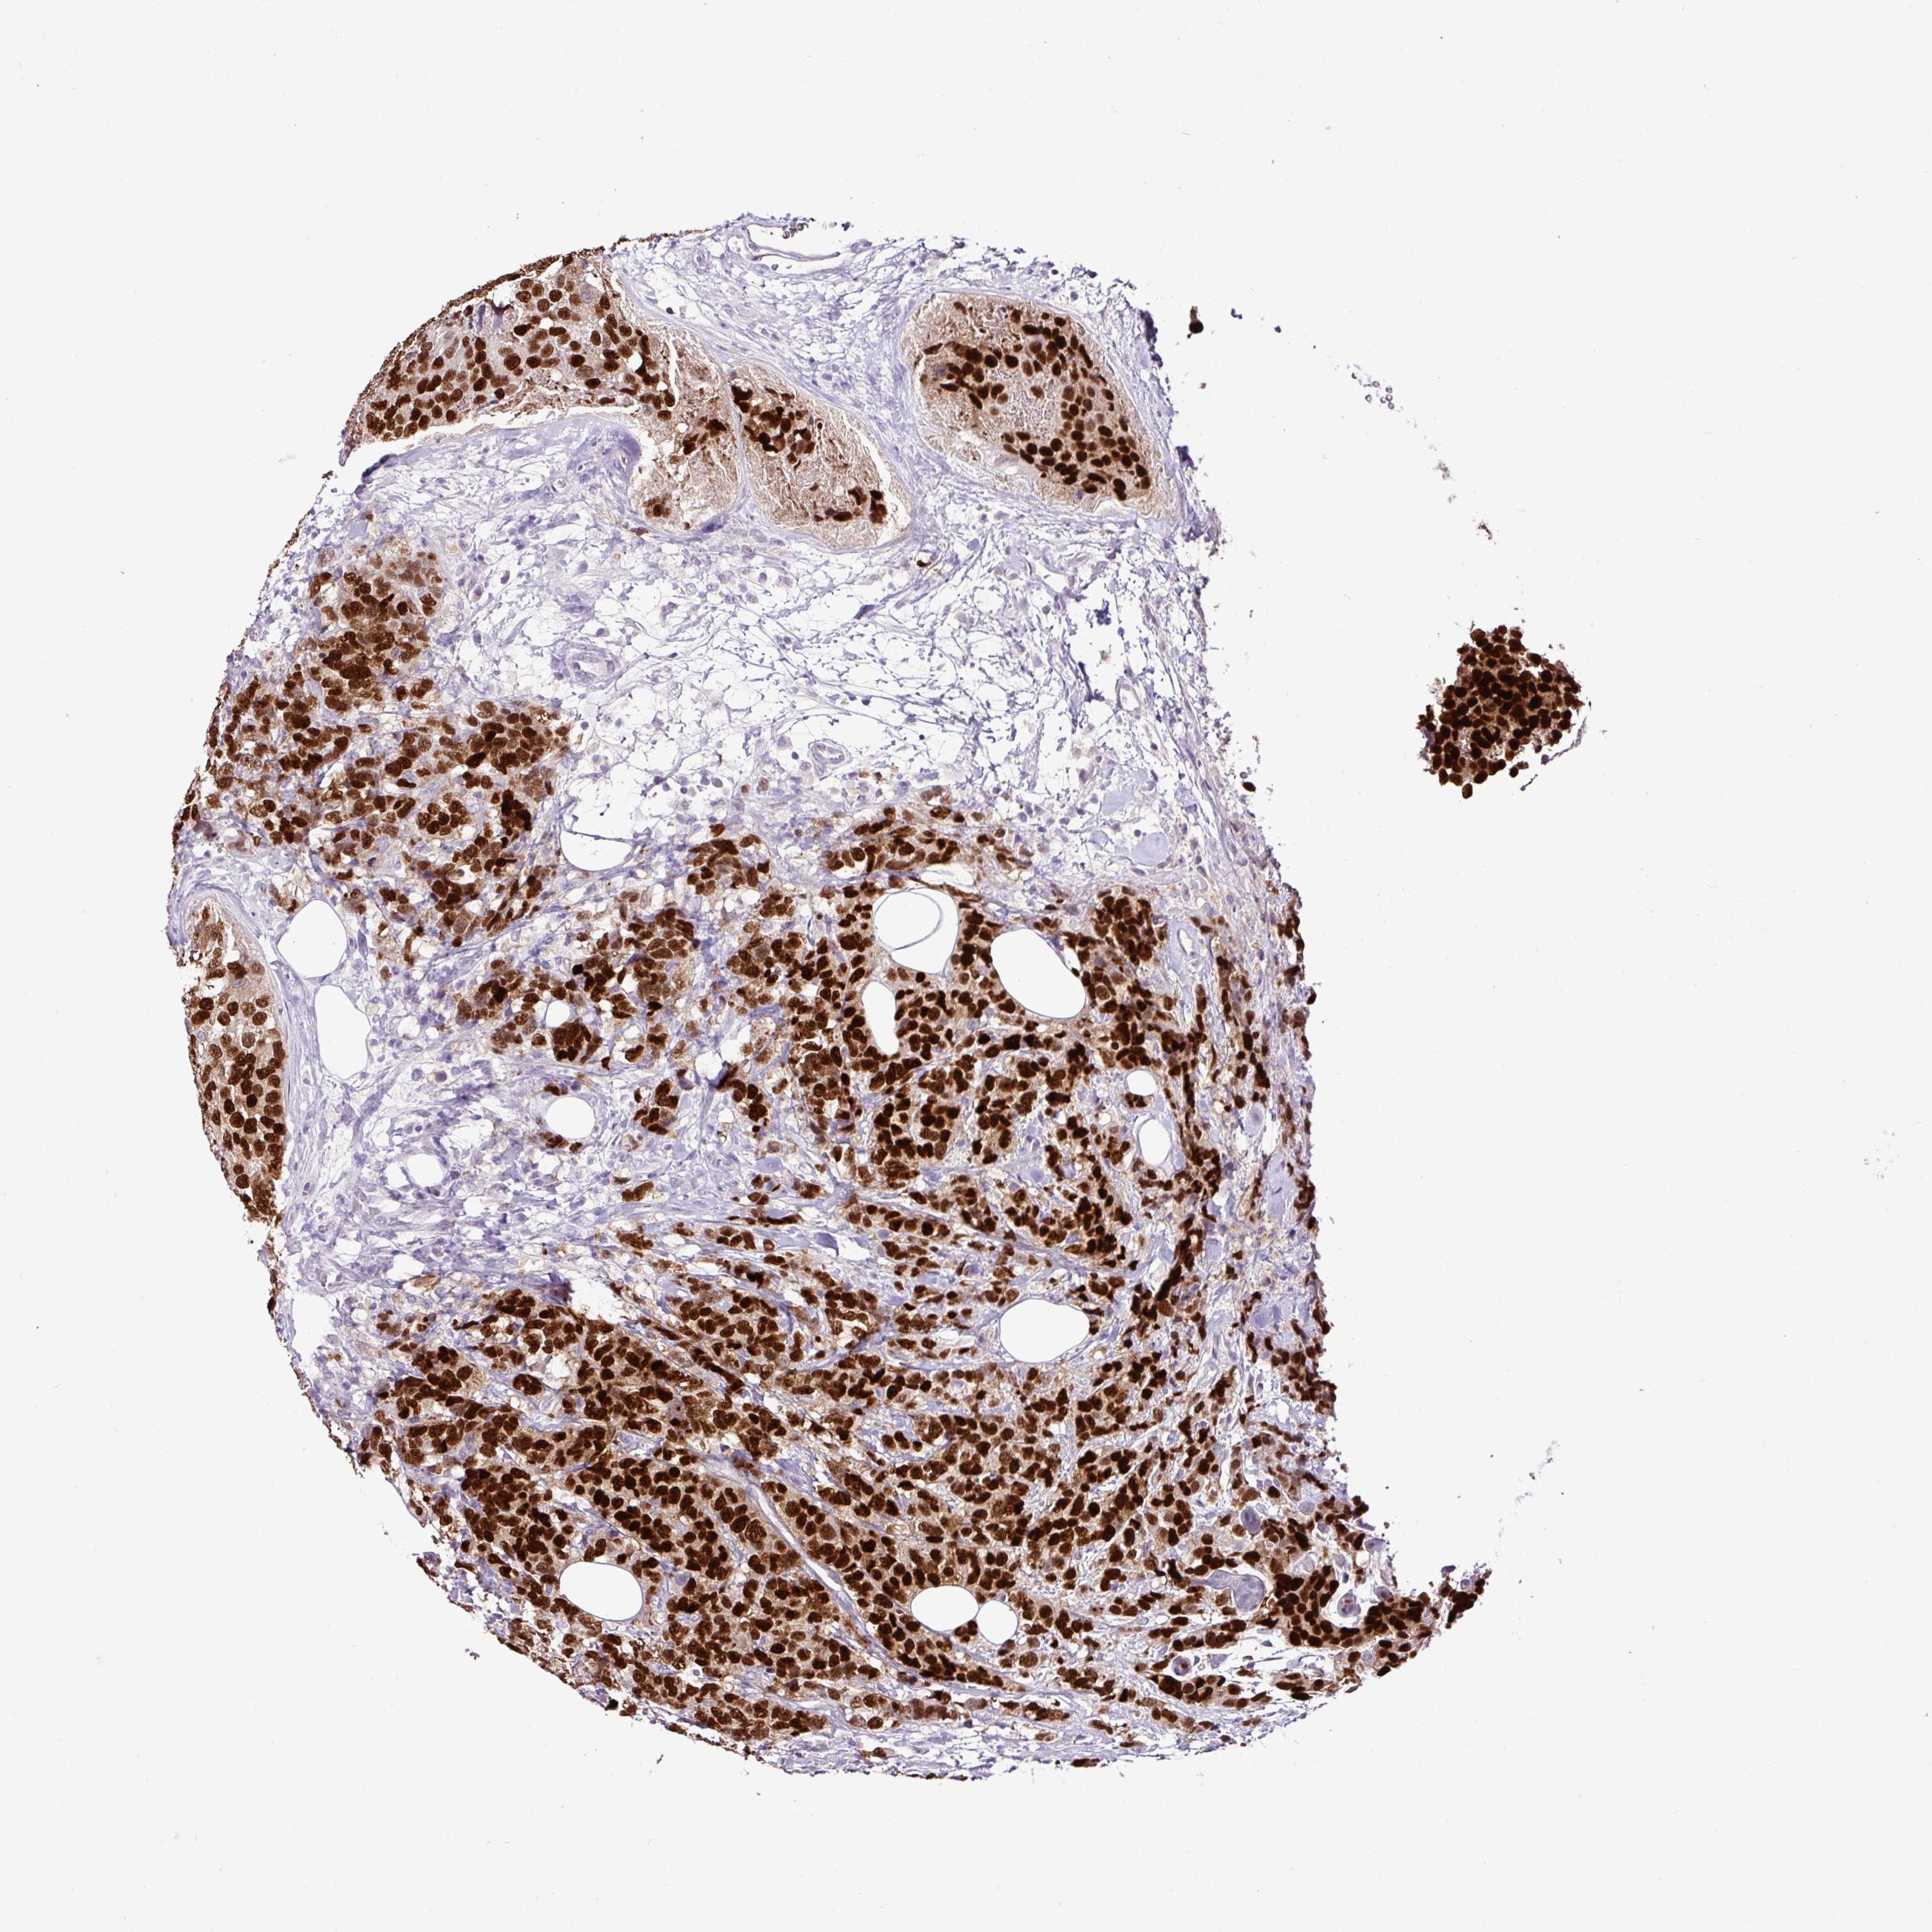

BRCA TCGA BRCA VALIDATION PROTEIN EXPRESSION

Breast cancer

Breast invasive carcinoma